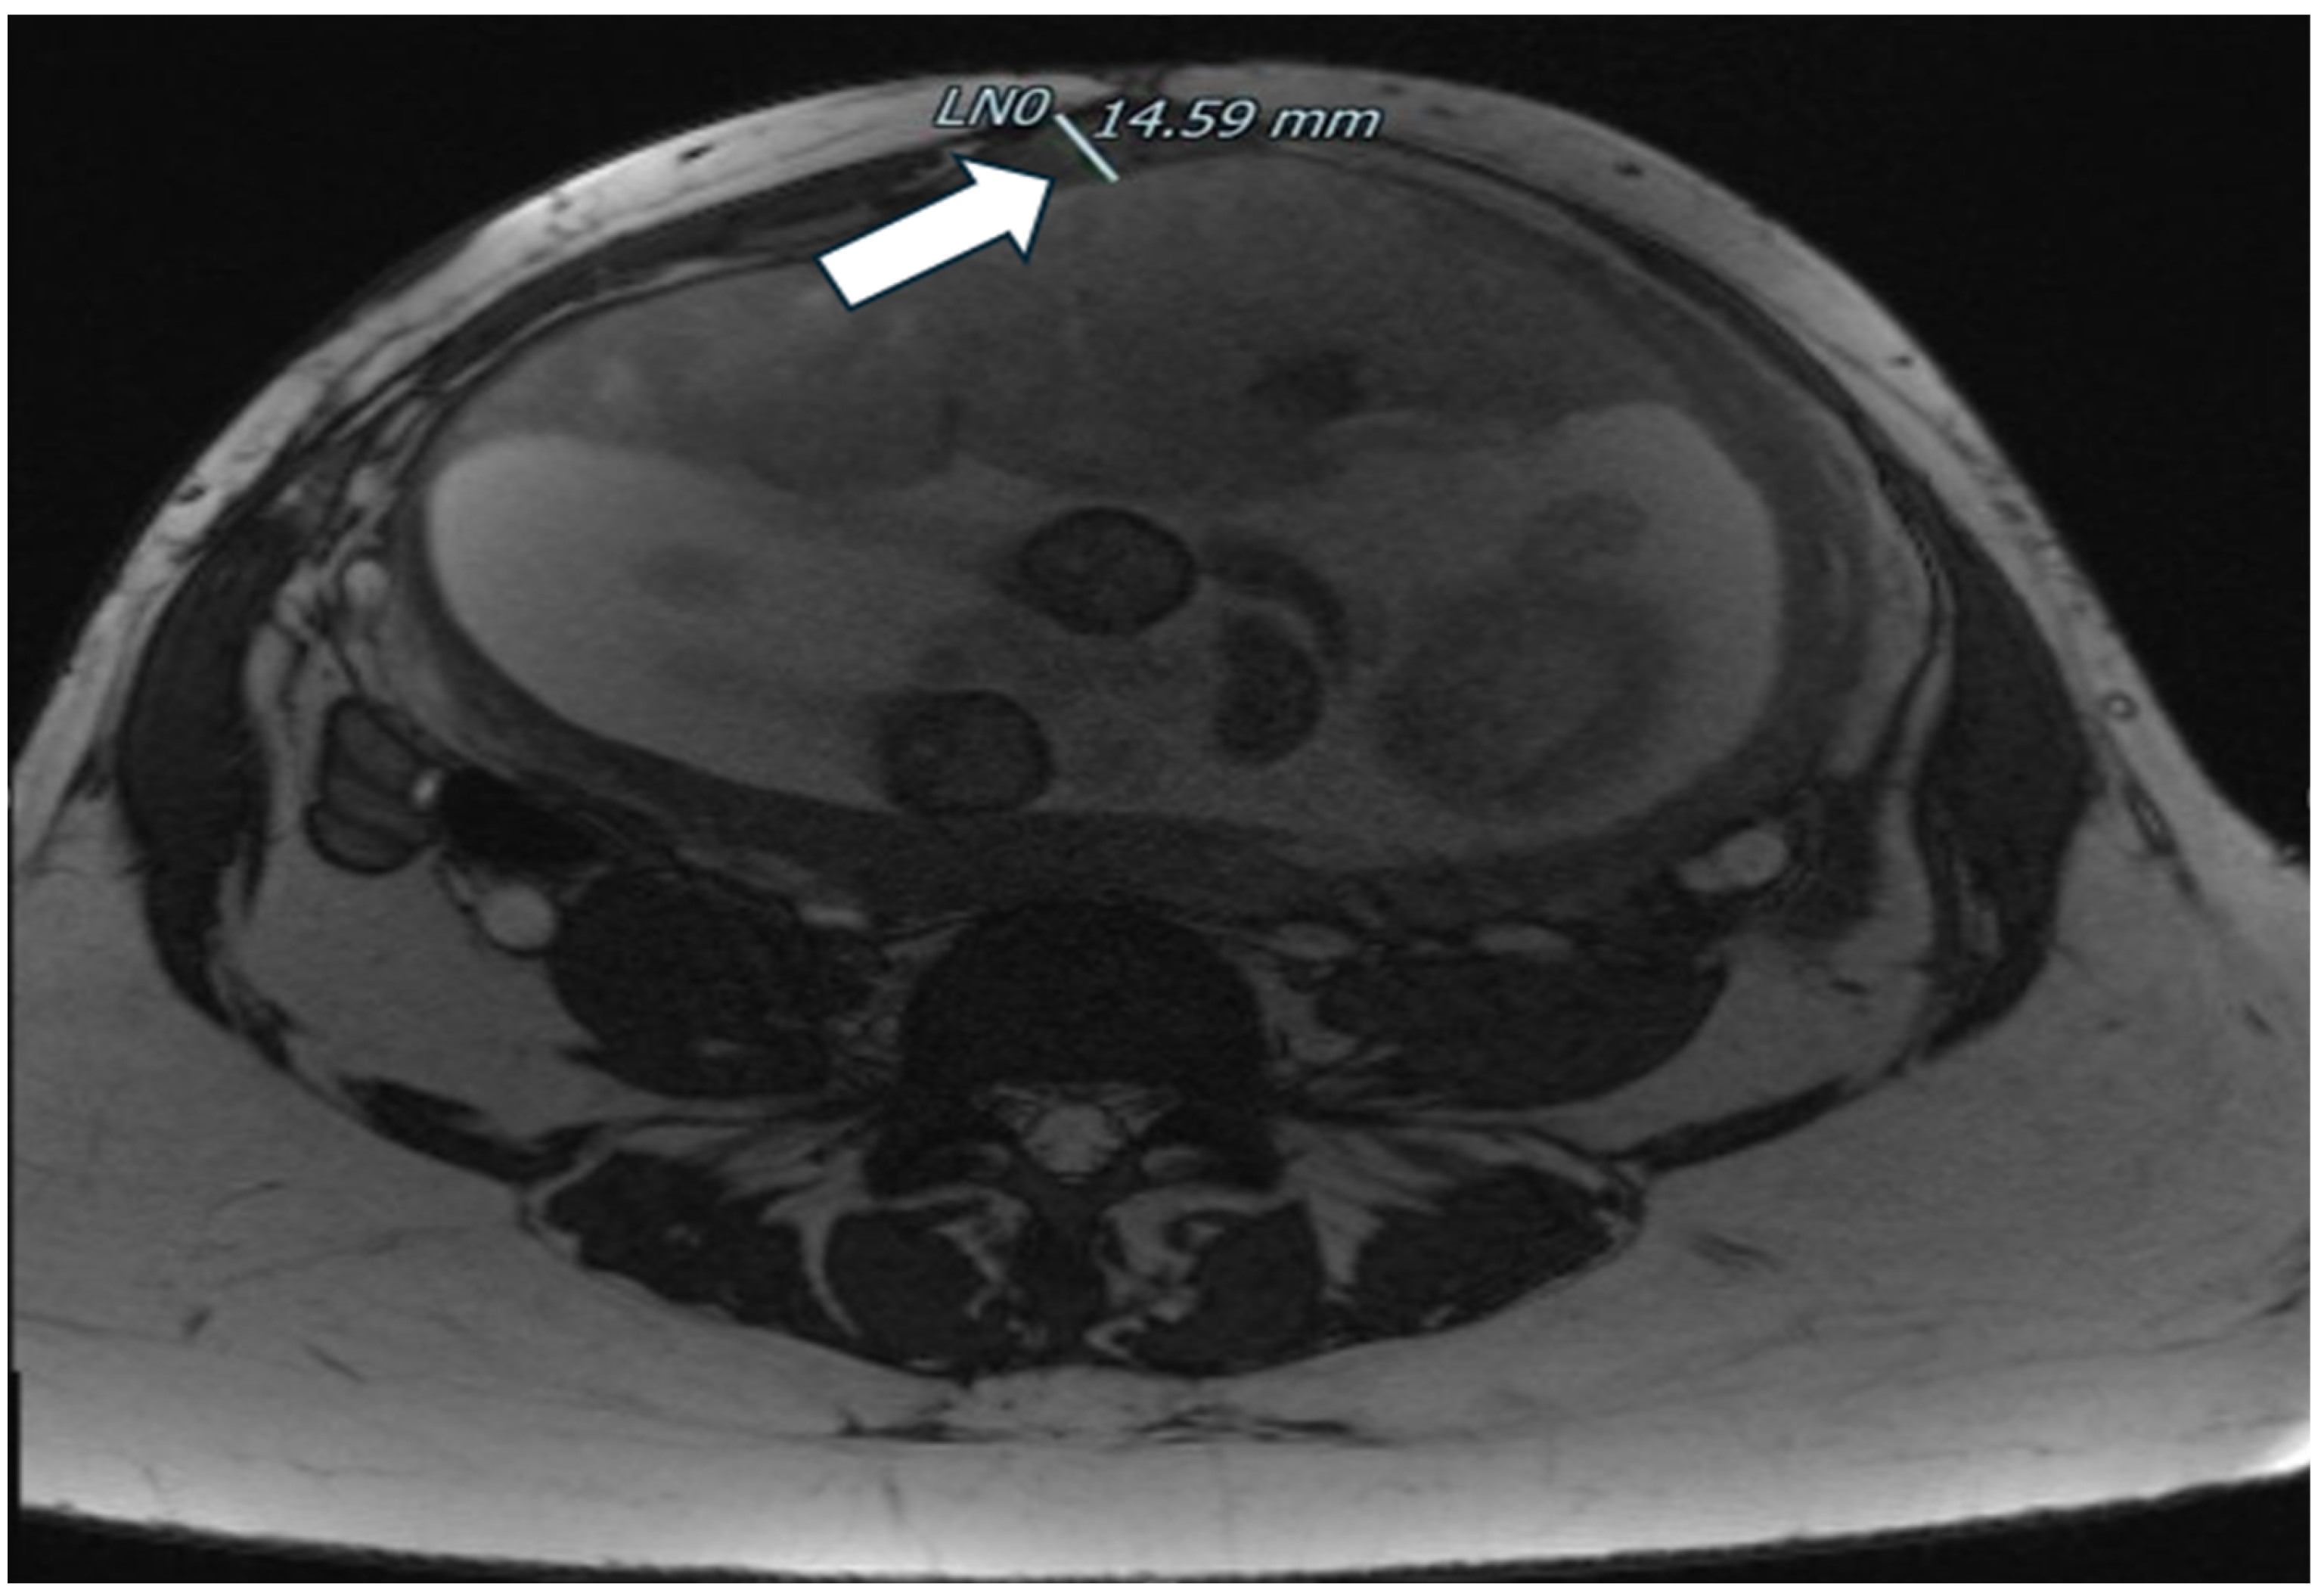

| Zermano S. et al. | 2024 | 29 1/7 | No | Yes | Yes | Yes | |